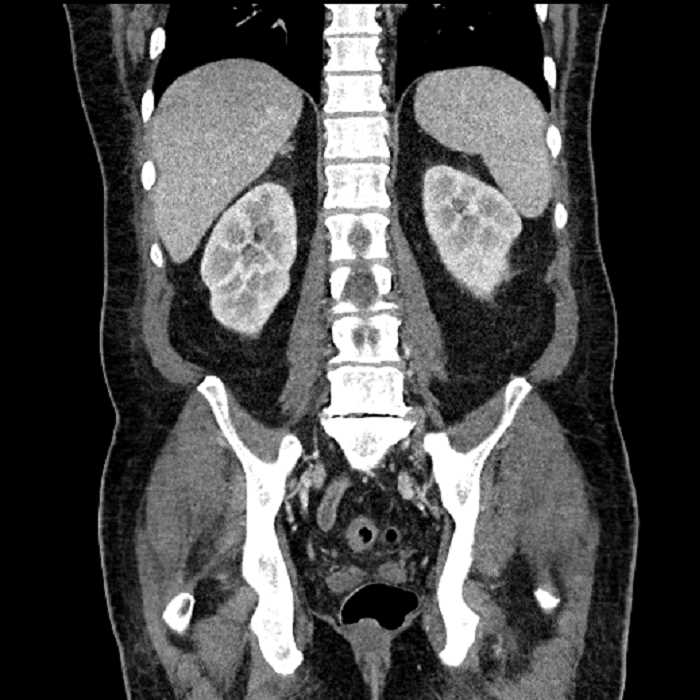

Age: 63

Sex: Male

Indication: Abdominal pain

• Large fluid density structure in hepatic segments 7 and 8 measuring 10 x 7 x 7 cm with internal septation and circumferential ill-defined low density compatible with edema

• Peripherally enhancing subcapsular collections along the anterior margin of the left hepatic lobe measuring 3 x 1 cm and 2 x 1 cm

• Clearly marginated fluid density structure in segment 7 and several other scattered tiny hypodensities, which likely represent cysts

• High grade stenosis of the left common iliac artery, with the left internal and external iliac arteries remaining patent

• Ankylosis of both sacroiliac joints

Acute sigmoid diverticulitis complicated by a small contained perforation and a large abscess in the right hepatic lobe. Additional small subcapsular abscesses along the anterior margin of the left hepatic lobe.

High grade stenosis of the left common iliac artery. The left external and internal iliac arteries are patent.